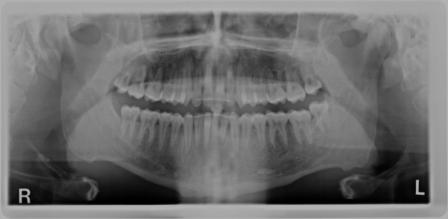

Nel nostro Studio impieghiamo un sistema radiografico computerizzato, il Vista Scan Plus della Dürr che consente di ottenere immagini di alta qualità (vedi confronto analogico/digitale) con dosi radiogene sensibilmente più basse per il paziente.

Con Vistascan Plus siamo in grado di ottenere, nel giro di pochi minuti, tutte le immagini che ci servono per un corretto ausilio diagnostico: bitewing, endorali, ortopantomografie, teleradiografie.